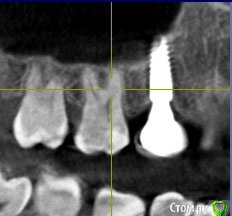

annda Опубликовано 5 января, 2015 Поделиться Опубликовано 5 января, 2015 (изменено) А формирователь какой стоит сейчас?высоту знаете?На КТ сейчас все абсолютно спокойно, там вроде даже мембрана на имплантате лежит( это нормально, они обрастают здоровой слизистой, если все идет по плану) Изменено 5 января, 2015 пользователем annda Ссылка на комментарий

Lyuba Опубликовано 5 января, 2015 Автор Поделиться Опубликовано 5 января, 2015 (изменено) не знаю, какой... извините за качество, во рту мобильником.....мембрана под вопросом, никто не утверждает есть или нет (смотрели с разных ракурсов, дескать, если есть "то очень тонкая")а периодонтитного процесса не видно? Вроде и с форума доктор Краснов говорил, что в этом районе все спокойно, но ведь отчего-то болит ((((Или нерв немного в соседнем зубе поврежден, но зуб живой??? Изменено 5 января, 2015 пользователем Lyuba Ссылка на комментарий

annda Опубликовано 5 января, 2015 Поделиться Опубликовано 5 января, 2015 (изменено) Боль в живых зубах , как правило, имеет весьма характерные признаки ( приступообразность, зависимость от температурных раздражителей, иррадиация по челюсти, зависимость от времени суток, интенсивность и т. д.).Не обязательно это будет прямо - таки сосед( там и через зуб есть проблемные изображения на КТ в переднем отделе)Постоянные не интенсивные ноющие боли могут быть связаны и с десной . Имплантат достаточно заглублен, потому все супраструктуры прилично прижимают мягкие ткани к костной , и это может вызывать достаточно сильный дискомфорт. Попросите поставить формирователь 4,5 мм, у Анкилоса есть такой, длинный и узкий, посмотрите, изменится что-то или нет.Ах да, периодонтитных процессов не вижу, да их и не может быть, раз зубы витальные.Периимплантита я лично тоже тут не вижу, может кто другой видит, так отпишется. Изменено 5 января, 2015 пользователем annda 2 Ссылка на комментарий

IvanK Опубликовано 5 января, 2015 Поделиться Опубликовано 5 января, 2015 это не узкий,уже, чем у Вас был (индивидуальный), но не самый узкий Ссылка на комментарий